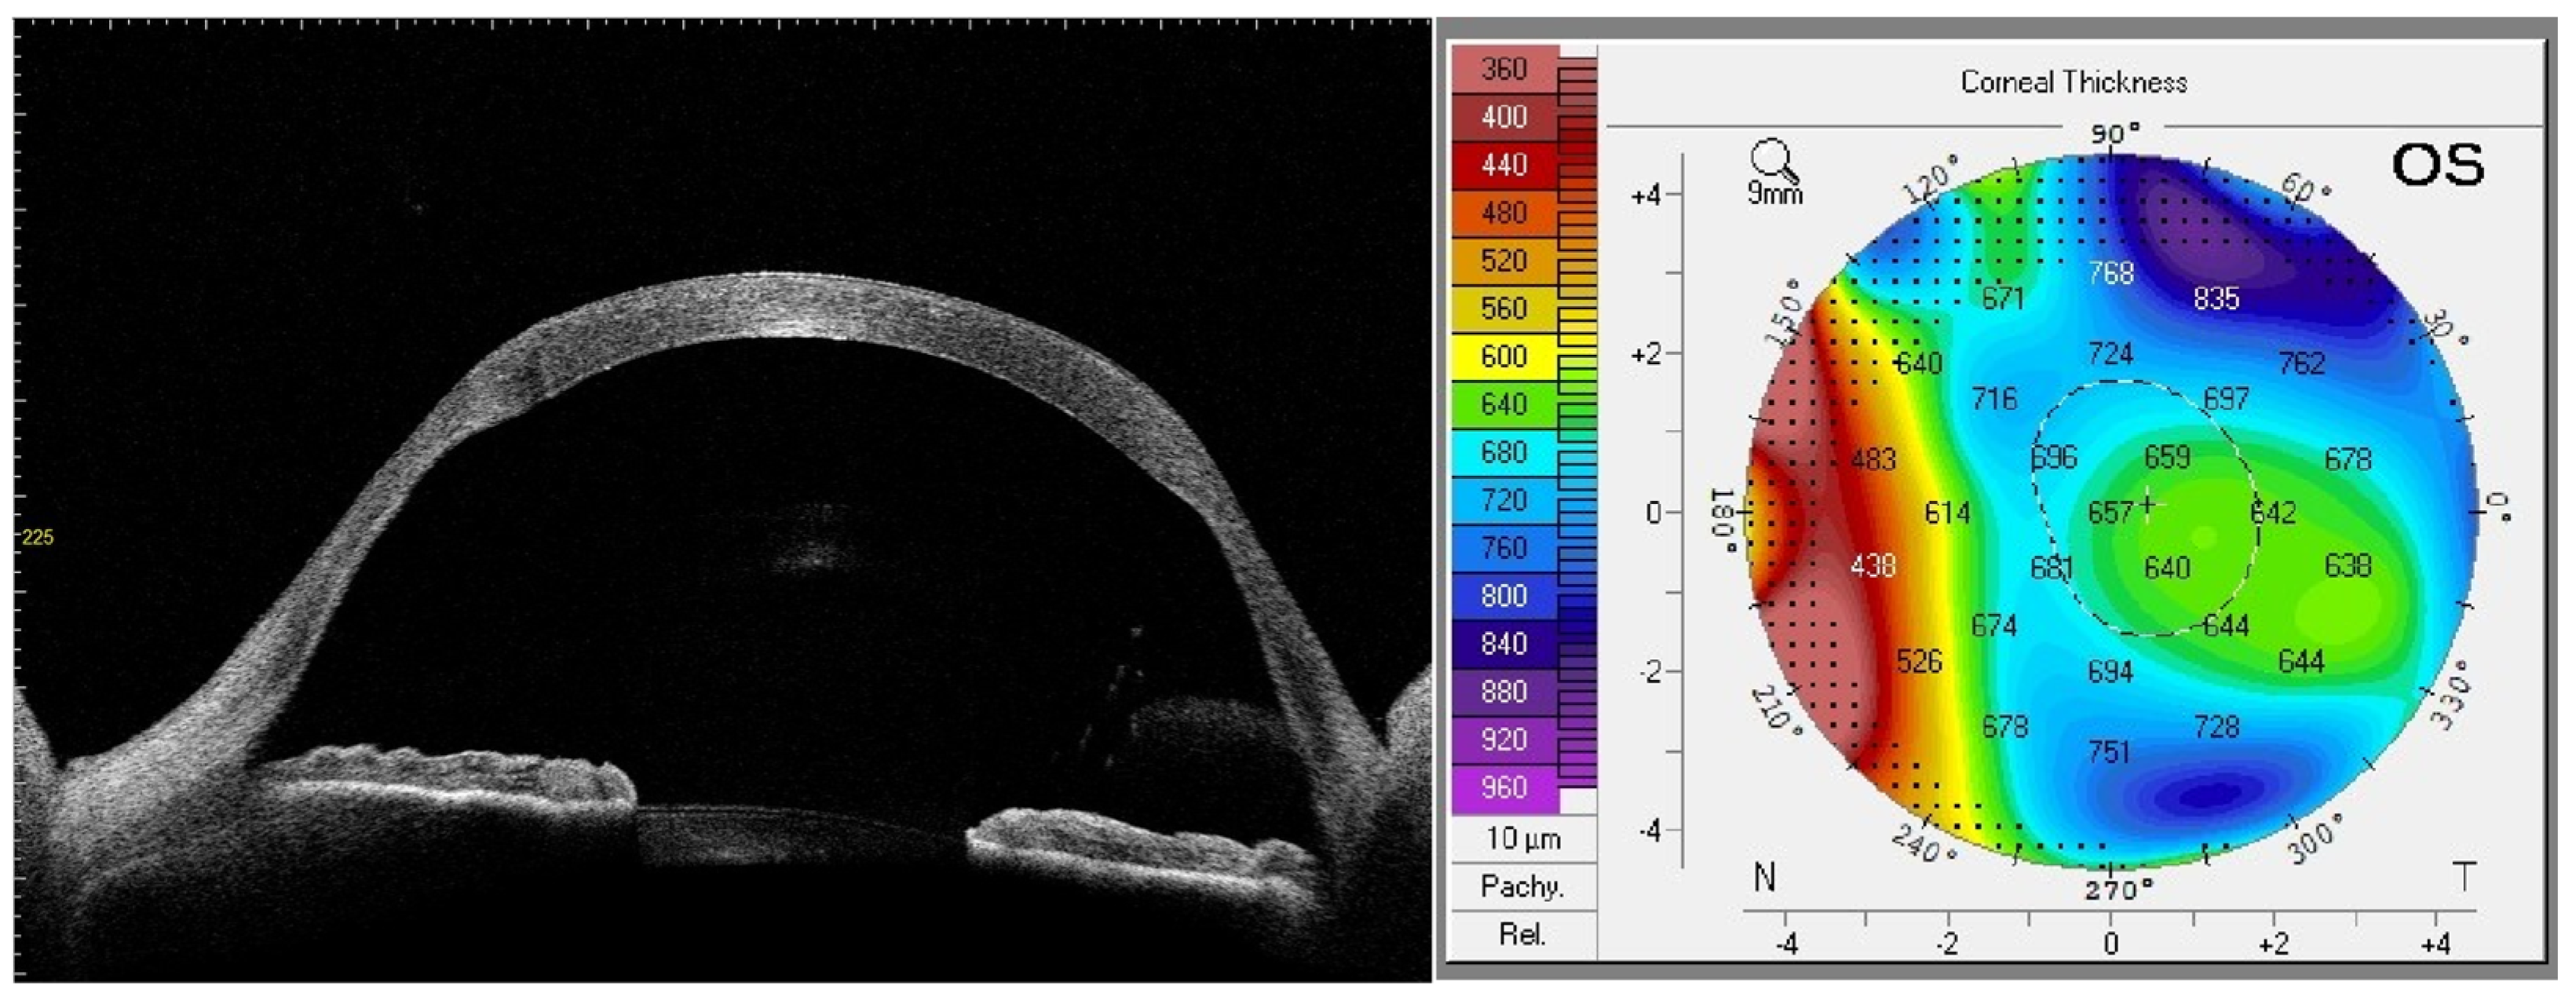

3.1. Preoperative Planning

4. Results